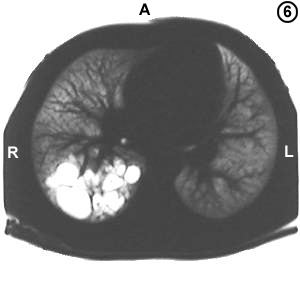

Corte Tomográfico " 6 "

El mismo Corte tomografico 2:

Semejante al anterior, Resolución tomografica para demostrar las cavidades quísticas que ahora se observan blancos en el parenquima pulmonar mas oscuro del corte tomografico N° 2.